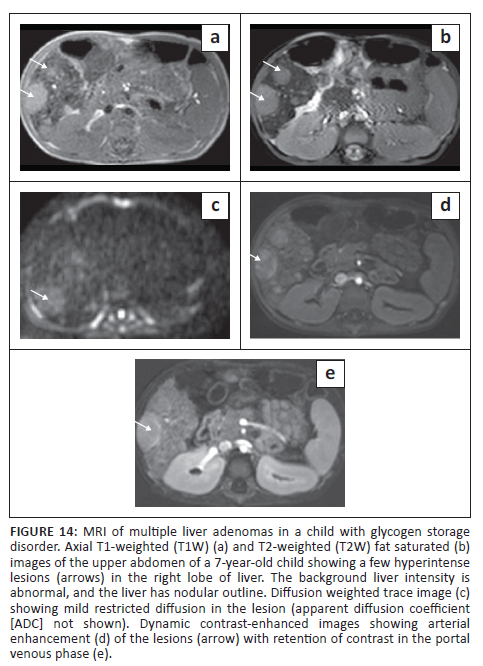

On MRI, HAs are usually heterogeneous on T1 and T2W images. The HNF-ɑ subtype, due to the presence of intracellular fat, can appear hyperintense on both T1W and T2W images with signal loss on chemical shift imaging.35 Post-contrast enhancement on MRI is very similar to that of CECT (Figure 14). Due to the presence of fat and arterial enhancement, these lesions have to be differentiated from fat-containing HCC. The presence of a pseudocapsule on the delayed phase in HCC can be used as a differentiating feature.33 Unlike FNH, HA shows hypointense signal on the hepatobiliary phase obtained after hepatocyte-specific contrast agents.33